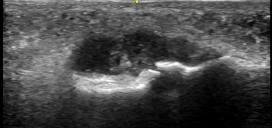

On point-of-care ultrasound (POCUS), a small joint effusion on the affected left big toe is seen with a maximum diameter of about 5mm.

An ultrasound guided arthrocentesis was performed using in-line needle visualization technique.

Ultrasound as a tool is highly effective in detecting joint fluid given its high sensitivity (Draghi et al), lack of radiation, cost effectiveness, and its use in rapid bedside assessment. To do so — use a linear probe to find the joint in the long axis and identify the hypoechoic fluid in relation to the joint space. Scan both in long and short axes to fully characterize the effusion. When performing a musculoskeletal ultrasound, you should always examine the affected joint as well as the contralateral unaffected side for comparison.

In our case, we were dealing with an effusion that measured 0.5cm by 2cm at its largest dimensions – it was a tiny effusion. Without the use of ultrasound, obtaining fluid from this tiny pocket would have been very difficult. The patient’s MTP was prepped using sterile procedure and an ultrasound probe cover was utilized to ensure sterility. We used in-line technique, as demonstrated in the above video.